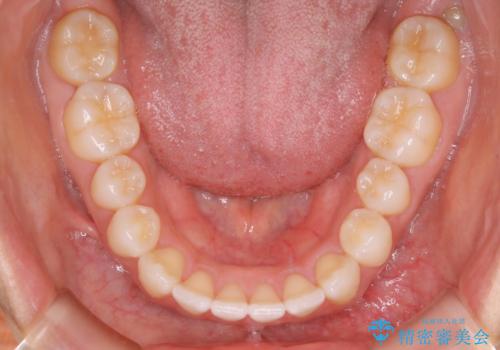

インビザライン矯正 前歯のすきっ歯を治したい

- 上顎の前歯のすきっ歯を治したいとのことで来院されました。

前歯の隙間を閉じる矯正治療の場合、インビザライン適用症例のためインビザラインによる治療をご提案しました。

後戻り防止のため、上唇小帯切除も併用しています。

上唇と歯ぐきを結ぶひも(上唇小帯)が長いと、前歯に隙間が空いてしまうことがあります。今回は隙間を確実に閉じる目的、また矯正後に再び隙間が空かないように、上唇小帯の切除も行っています。